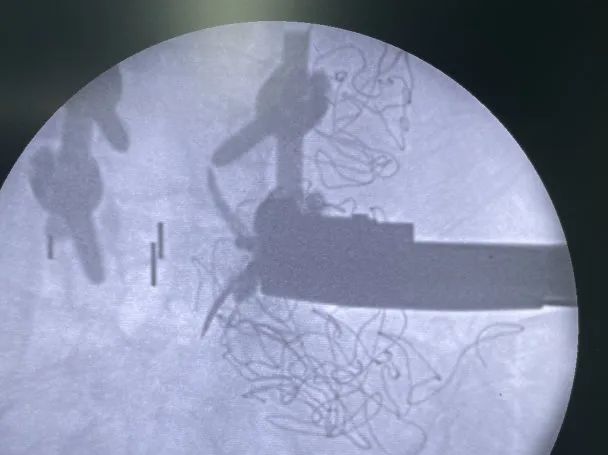

患者右側(cè)臥位,透視確認(rèn)皮膚切口區(qū)域

切皮暴露,透視確認(rèn)手術(shù)節(jié)段

最終透視